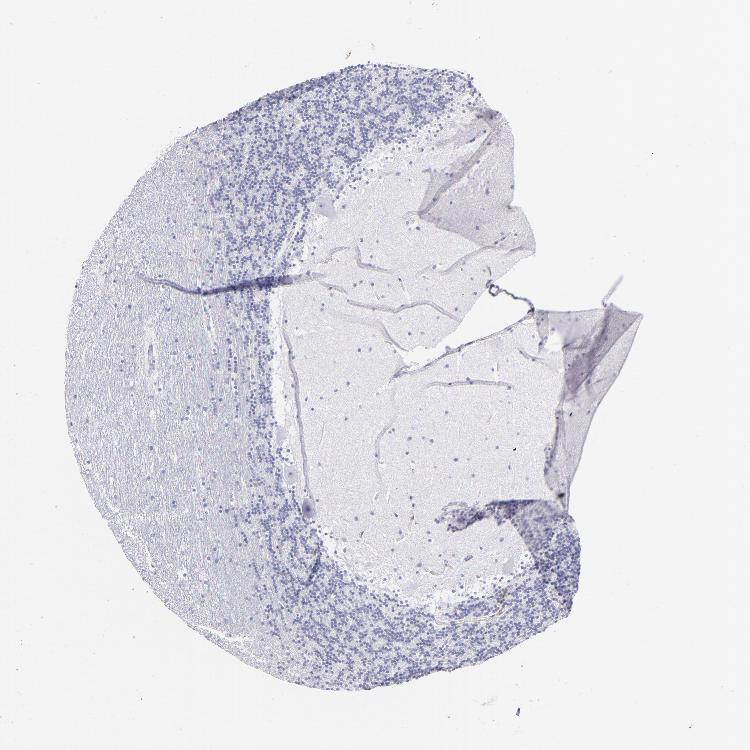

CEREBELLUM - Antibody stainingi

Antibody staining in the annotated cell types in the current human tissue is reported as not detected, low, medium, or high, based on conventional immunohistochemistry profiling in selected tissues. This score is based on the combination of the staining intensity and fraction of stained cells.

Each image is clickable and will lead to virtual microscopy that enables deeper exploration of all samples and also displays staining intensity scores, fraction scores and subcellular localization as well as patient and tissue information for each sample.

Antibody HPA009177Antibody CAB002661

Purkinje cells Not detectedNot detected

Cells in granular layer Not detectedNot detected

Cells in molecular layer Not detectedNot detected